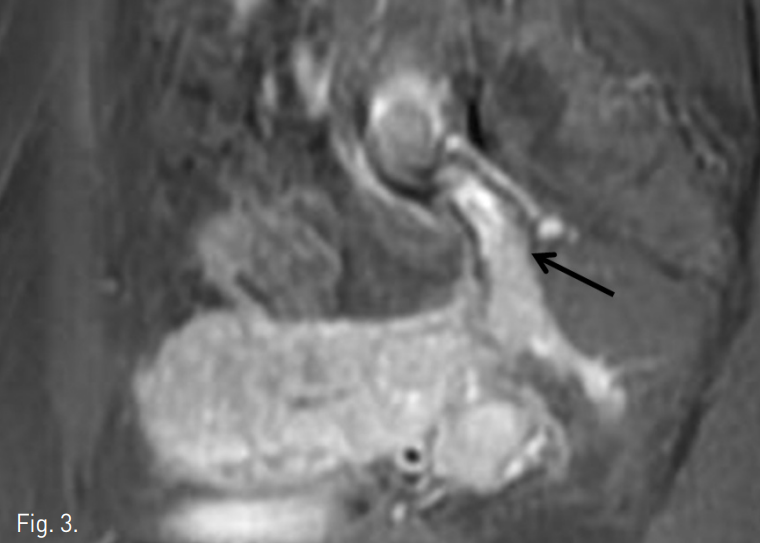

초음파 유도하에 우측대퇴정맥을 천자하여 5Fr sheath (Terumo, Tokyo, Japan)를 삽입하였다. Cobral 카테터(Cook, Bloonington, IN, USA)를 좌측 내골정맥에 위치시킨 뒤 골반조영술을 시행한 결과, 혈관 내 타원형의 충만 결손이 보였다(Fig 3).

Fig. 3

Venogrm reveals multiple filling defects (arrows) in internal iliac vein, which is consistent with intravenous leiomyomatosis.